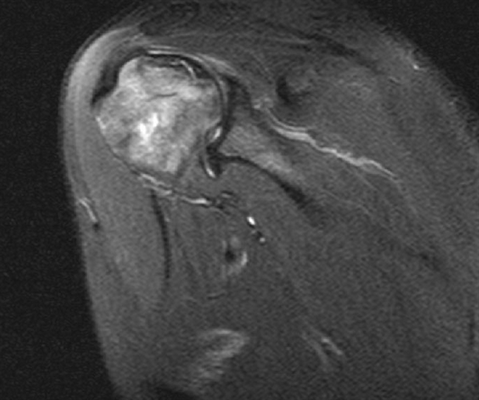

На серии МР-томограмм, взвешенных по Т1 и Т2, а также протонной плотности с использованием режима жироподавления в аксиальной, косой корональной и косой сагиттальной плоскостях определяются структуры правого плечевого сустава. Соотношение в суставе на момент исследования не нарушено. Субакромиальное пространство составляет 6 мм (сужено). Суставная впадина лопатки уплощена, контуры ее ровные, с признаками субкортикального остеосклероза. По краям суставной впадины лопатки имеются небольшие остеофиты. Головка плечевой кости округлой формы не деформирована. Суставной хрящ неоднородной структуры, неравномерно истончен, целостность его не нарушена.

Суставная губа на всем протяжении прослеживается, дегенеративно изменена, без отчетливых признаков нарушения целостности. Средняя суставно-плечевая связка неравномерно утолщена, без нарушения целости, но вокруг отмечается небольшое количество выпота. Сухожилие надостной мышцы на протяжении 24 мм (преимущественно в области мышечного брюшка) утолщено, разволокнено с признаками отека и участками обызвествления, преимущественно изменения отмечаются в передней порции волокон - повреждение сухожилия дегенеративного генеза. Вокруг мышечного брюшка надостной мышцы отмечается небольшой отек межмышечной клетчатки.

Сухожилие подлопаточной мышцы в области прикрепления к малому бугорку плечевой кости утолщено, минимально разволокнено, общая целость его и натяжение сохранены (изменения по типу тендиноза). Сухожилия подостной мышцы в области прикрепления к плечевой кости имеют неоднородную МР- структуру, за счет дегенеративных изменений, целость не нарушена. Сухожилия малой круглой мышцы не изменено. Визуализируется умеренное скопление свободной жидкости в полости плечевого сустава, умеренное в подклювовидной сумке. Сухожилия длинной головки двуглавой мышцы плеча не изменено, вдоль него минимальное количество выпота. Правый акромиально-ключичный сустав дегенеративно изменен: суставные поверхности имеют неровные контуры с наличием краевых костных разрастаний, сами суставные концы с субкортикальным остеосклерозом. Капсула сустава умеренно утолщена.

ЗАКЛЮЧЕНИЕ: МР-картина остеоартроза правого плечевого и акромиально-ключичного сустава I-II ст., признаков импинджмент синдрома с частичным повреждением сухожилия надостной мышцы, умеренно выраженные дегенеративные изменения сухожилия подлопаточной мышцы по типу тендиноза. Синовит. Умеренный теносиновит.